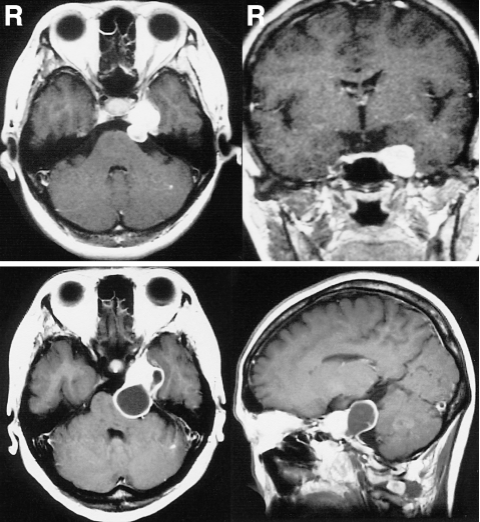

38岁女性绫子因左侧面部感觉异常就医。磁共振成像显示为哑铃状肿瘤,明显增强(图1上排)。肿瘤较实,主要位于左中颅窝,三叉神经根是肿瘤的明显起源,并经Meckel’s腔延伸至后窝。根据我们对三叉神经鞘瘤的分类,诊断为MP型,代表三叉神经鞘瘤的中后颅窝位置。肿瘤大小2.5×1.8×2.0cm。由于患者要求,最终行GKR。整个肿瘤在50%等剂量体积内(图2)。最大辐射剂量为28Gy,边际辐射剂量为14Gy。然而,随访MRI显示肿瘤囊肿形成,GKR后15个月肿瘤增大。患者于GKR术后18个月开始主诉左外展神经麻痹导致左侧面部疼痛和复视,转院治疗。

图1:(上排)伽玛刀放射治疗(GKR)前轴位和冠状位t1加权磁共振(MR)增强图显示左侧中窝和左侧后窝肿瘤,外观坚实,强化均匀。(下排)GKR术后18个月,轴位和矢状位t1加权钆成像显示肿瘤包含多个囊肿,并明显压迫脑干,囊肿后部周围有假囊,与后颅窝硬脑膜相连。

入院时,MR示左侧中后颅窝一哑铃状肿瘤,t1低强度,t2高强度。肿块内有多个囊肿,实性部分增强均匀。肿瘤后部形成囊肿,囊部强化,与后颅窝硬脑膜连续,明显压迫脑干,肿瘤大小为4.5×2.5×2.5cm(图1下排)。